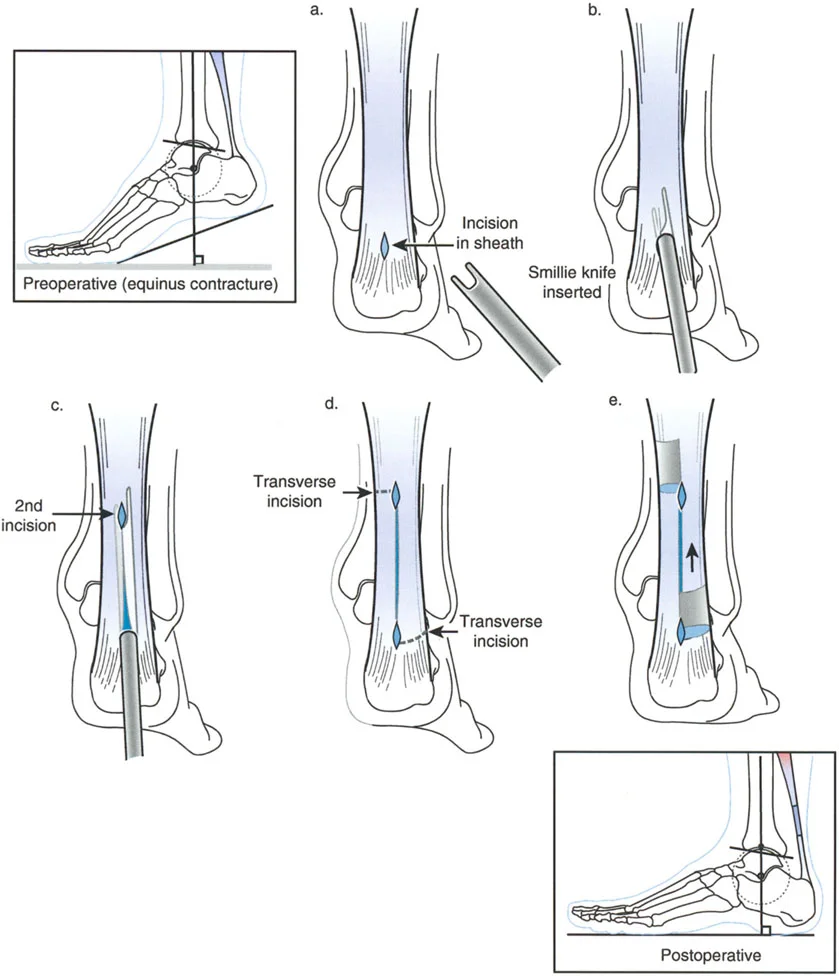

تطويل وتر العرقوب (Achilles Tendon Lengthening)

هذه العملية ضرورية عندما يكون وتر العرقوب قصيرًا ومشدودًا، مما يحد من حركة ثني القدم للأعلى.

- تطويل وتر العرقوب بالشق الجلدي (Percutaneous Z Tendo Achillis Lengthening):

- تُفضل هذه الطريقة في حالات تقوس الكاحل الناتج عن قصر وتر العرقوب فقط، لتجنب التطويل المفرط للوتر.

- يتم إجراء شقوق صغيرة في الجلد وإدخال مشرط خاص (Smillie knife) لعمل شقوق طولية وعرضية في الوتر، مما يسمح له بالتطويل التدريجي مع ثني القدم للأعلى.

- الميزة هي الحفاظ على غمد الوتر سليمًا، مما يساعد على التئام الوتر مع الحفاظ على التوتر.

- صورة توضح طريقة الشق الجلدي لتطويل وتر العرقوب.

- صور متتالية توضح خطوات عملية تطويل وتر العرقوب بالشق الجلدي.